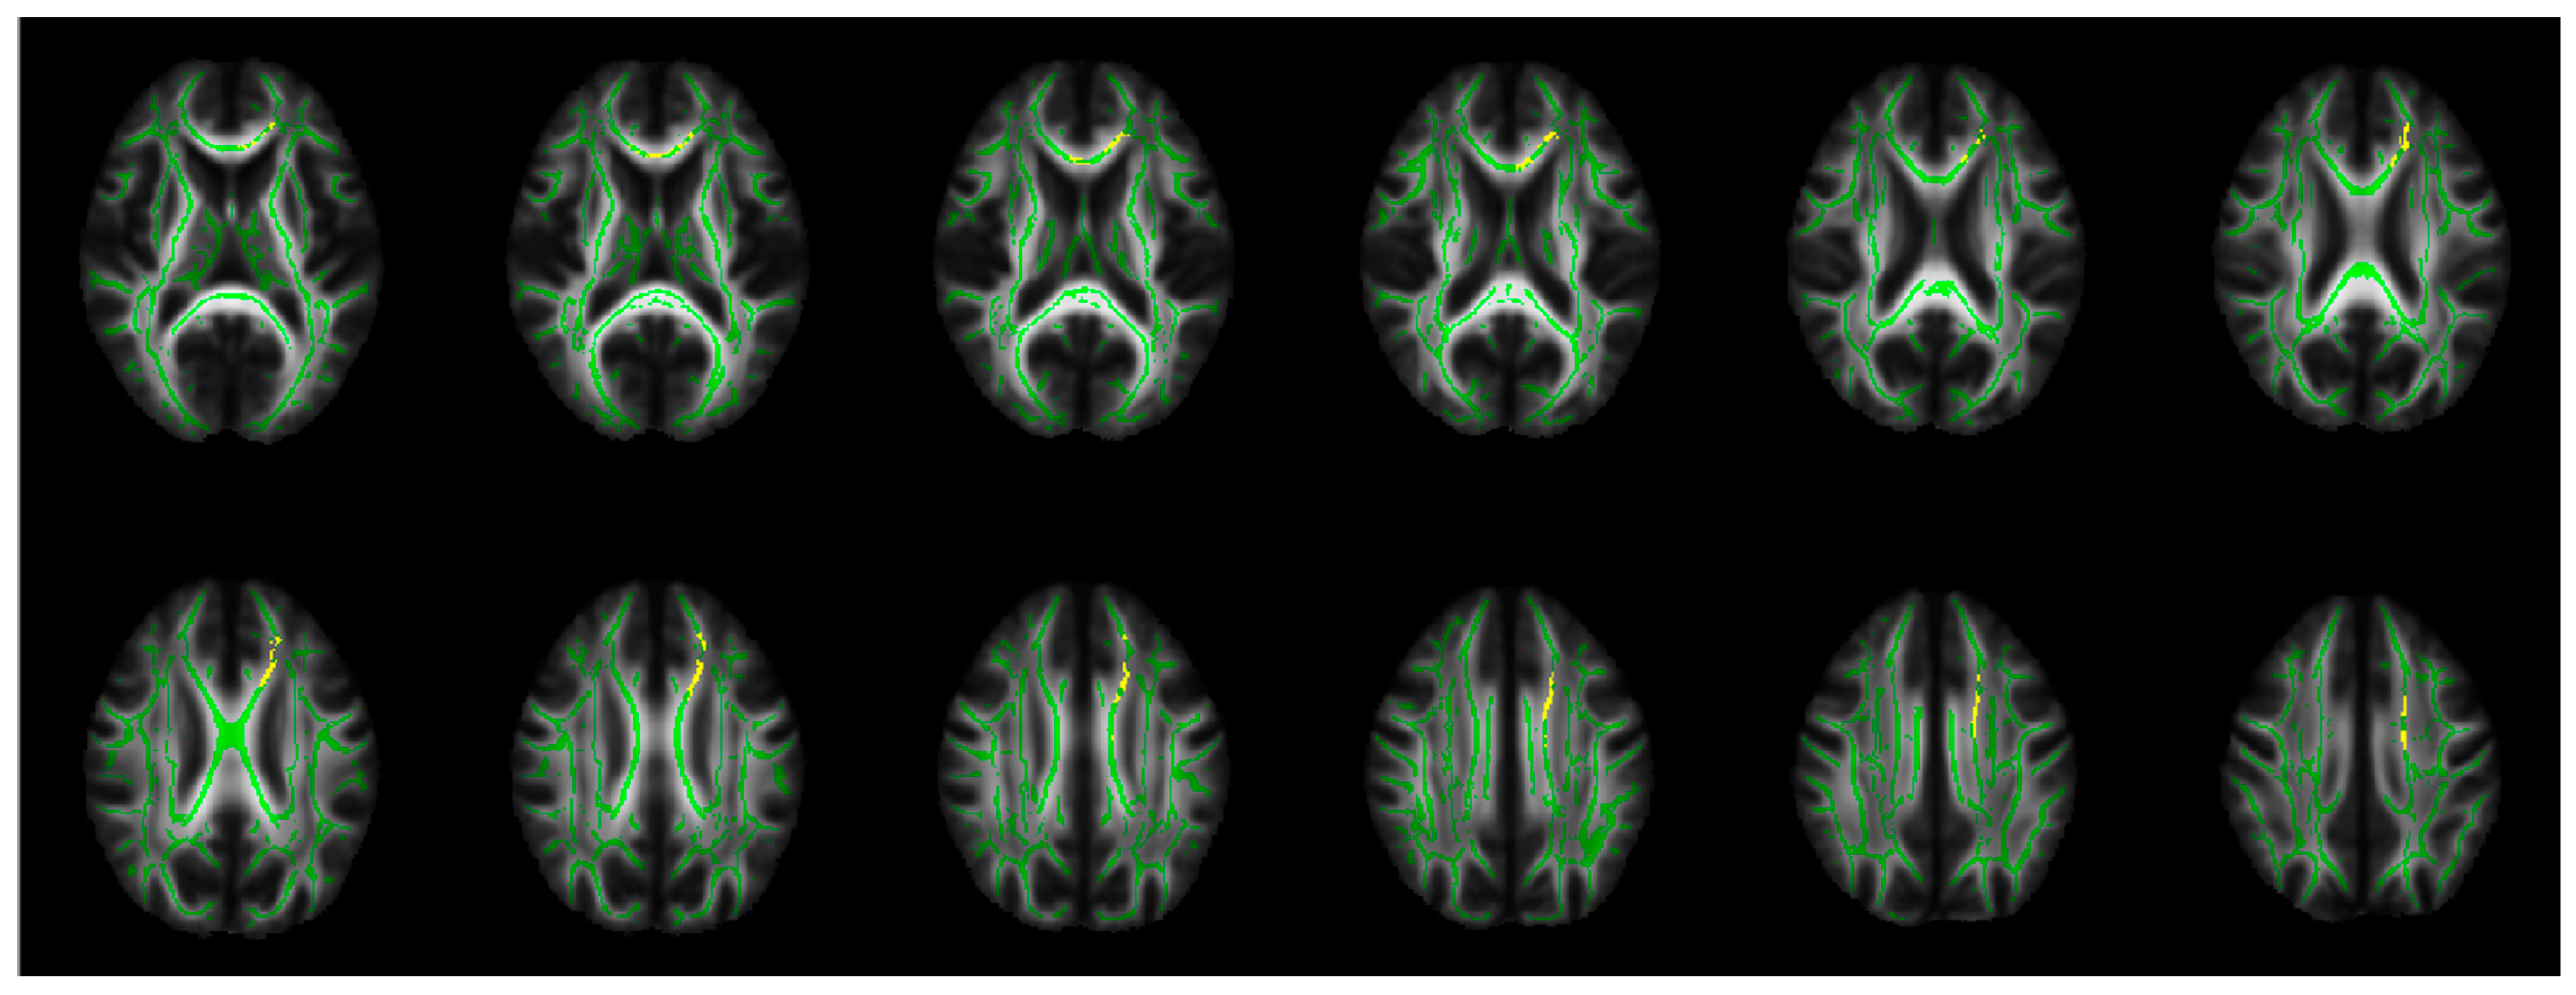

Using the FSL command “cluster”, the most significant 845 connected voxels (ptfce-FWE < 0.005) were defined as TBSS-ROI from the corrected p-value image, showing significantly increased RD in PBD compared to HC. These voxels were distributed not in all WM tracts but in confined regions of the mean FA skeleton, corresponding to the bCC, left gCC, ACR, and SCR, extending to the SFG-WM (Figure 2).

Figure 2.

TBSS-ROI (yellow). The most significant 845 connected voxels showing increased RD in PBD compared to HC (ptfce-FWE < 0.005) in the TBSS analyses, overlaid on the mean FA skeleton (green) and mean FA map. FA: fractional anisotropy; HC: healthy control; PBD: psychotic bipolar disorder; ptfce-FEW: corrected p-value for multiple comparisons across voxels by family-wise error (FWE) corrections using threshold-free cluster enhancement (TFCE); RD: radial diffusivity; TBSS: tract-based spatial statistics.

In the present study, the TBSS analyses exhibited increased RD in widespread WM tracts in PBD compared to HC (Table 2 and Figure 1). The most disrupted WM regions (TBSS-ROI) were distributed in confined regions in the bCC, left gCC, ACR, and SCR, extending to the SFG-WM (Figure 2). Decreased FA and increased RD in PBD compared to NPBD were detected in TBSS-ROI (Table 3).